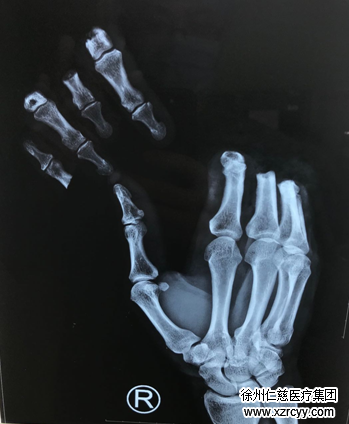

6月5日下午1时许,43岁的杨明(化名)正在家中忙碌,丝毫没想到几分钟后,一场巨大的厄运就会降临。几分钟后,只听杨明“哎呦”一声,杨明的右手2-5指被“裁剪刀”齐齐的切了下来,鲜血如泉涌。家人看到4个手指静静的躺在桌子上,差点晕倒,迅速把杨明送往当地医院,当地医院的急诊医生拆开杨明右手的包布,也不由倒吸一口冷气,急诊医生告诉杨明家人:想接上断指的话需要进行显微外科手术,建议送到淮海经济区手外伤专科医院betway在线登陆治疗。于是杨明又被一路疾驰送到我院。

迅捷的术前准备后,杨明被推入手术室,朱辉、黎章灿、李海建手术团队协力合作,为患者实施了“右手2-5指清创再植”手术。

由于患者离断指体较多,缺血时间较长,从傍晚到次日凌晨,经过数个小时的努力,手术获得成功,患者的断指都接上了。在手术室外苦苦等待的家属,看到手术室门打开,看到被接上手指的杨明被推出来,激动得热泪盈眶。